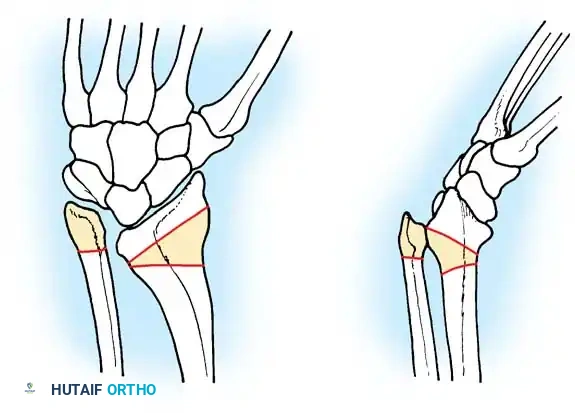

Radiographic evaluation of camptodactyly. Note the absence of primary osseous dysplasia in early stages, though secondary joint remodeling may occur in long-standing cases.

Most patients present during the first year of life. Approximately two-thirds have bilateral involvement, though severity is often asymmetrical.

The classic posture includes PIP joint flexion with compensatory MCP joint hyperextension. Rotational deformities may cause mild overlapping of the fingers.

Evaluate the PIP joint while passively flexing and extending the wrist. In young children with a shortened FDS, the PIP deformity will disappear or significantly improve when the wrist is flexed. In older children, the deformity usually becomes fixed due to secondary volar plate and collateral ligament contractures.

If left untreated, 80% of cases worsen, particularly during periods of rapid skeletal growth. Progression typically halts after skeletal maturity (age 18 to 20 years).

Camptodactyly with a severe flexion deformity of 80 degrees when the wrist is held in extension.

The same patient demonstrating improvement of the deformity to 40 degrees upon passive wrist flexion, indicating a tight FDS unit.

Preoperative planning diagram for a comprehensive volar release, highlighting the structures contributing to the flexion contracture.